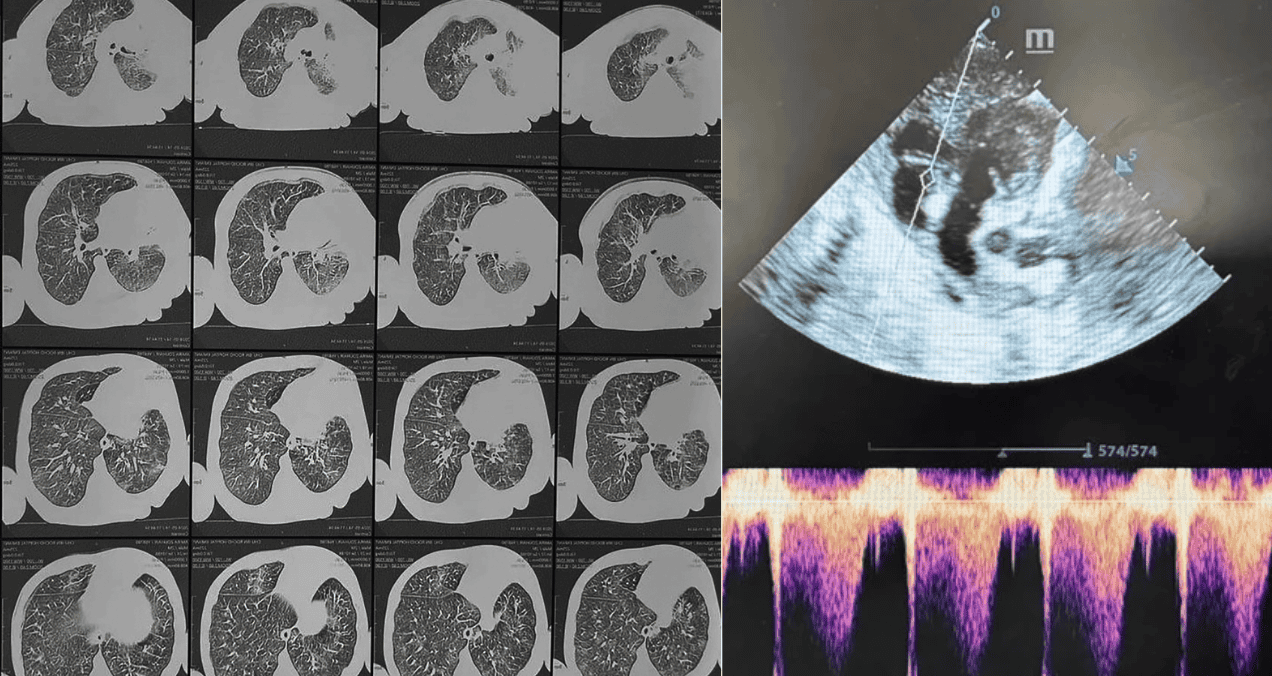

La PCR, paradójicamente normal (0.6 mg/L), no restó gravedad al cuadro. La RT-PCR confirmó la presencia de la bacteria Bordetella pertussis, y la tomografía torácica evidenció neumonía alveolointersticial con atelectasia del lóbulo medio. El hallazgo crucial llegó con la ecocardiografía: hipertensión pulmonar (PAPs 46 mmHg) sin cardiopatía estructural, secundaria a la infección.

Ecocardiograma que revela hipertensión pulmonar con una presión de 46 mmHg

A las tres semanas, la presión pulmonar descendió a 32 mmHg, y la leucocitosis se normalizó. La paciente requirió 25 días de hospitalización pero evolucionó favorablemente, con desarrollo psicomotor adecuado a los 4 meses de seguimiento.